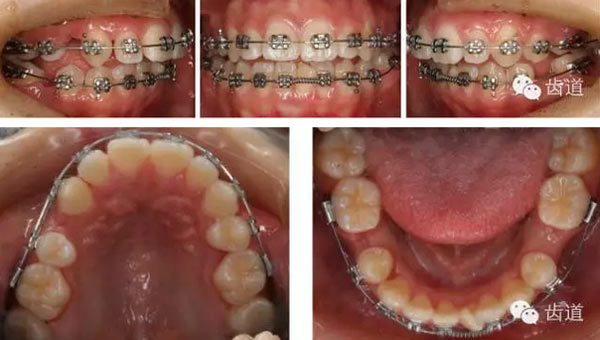

矯治過(guò)程